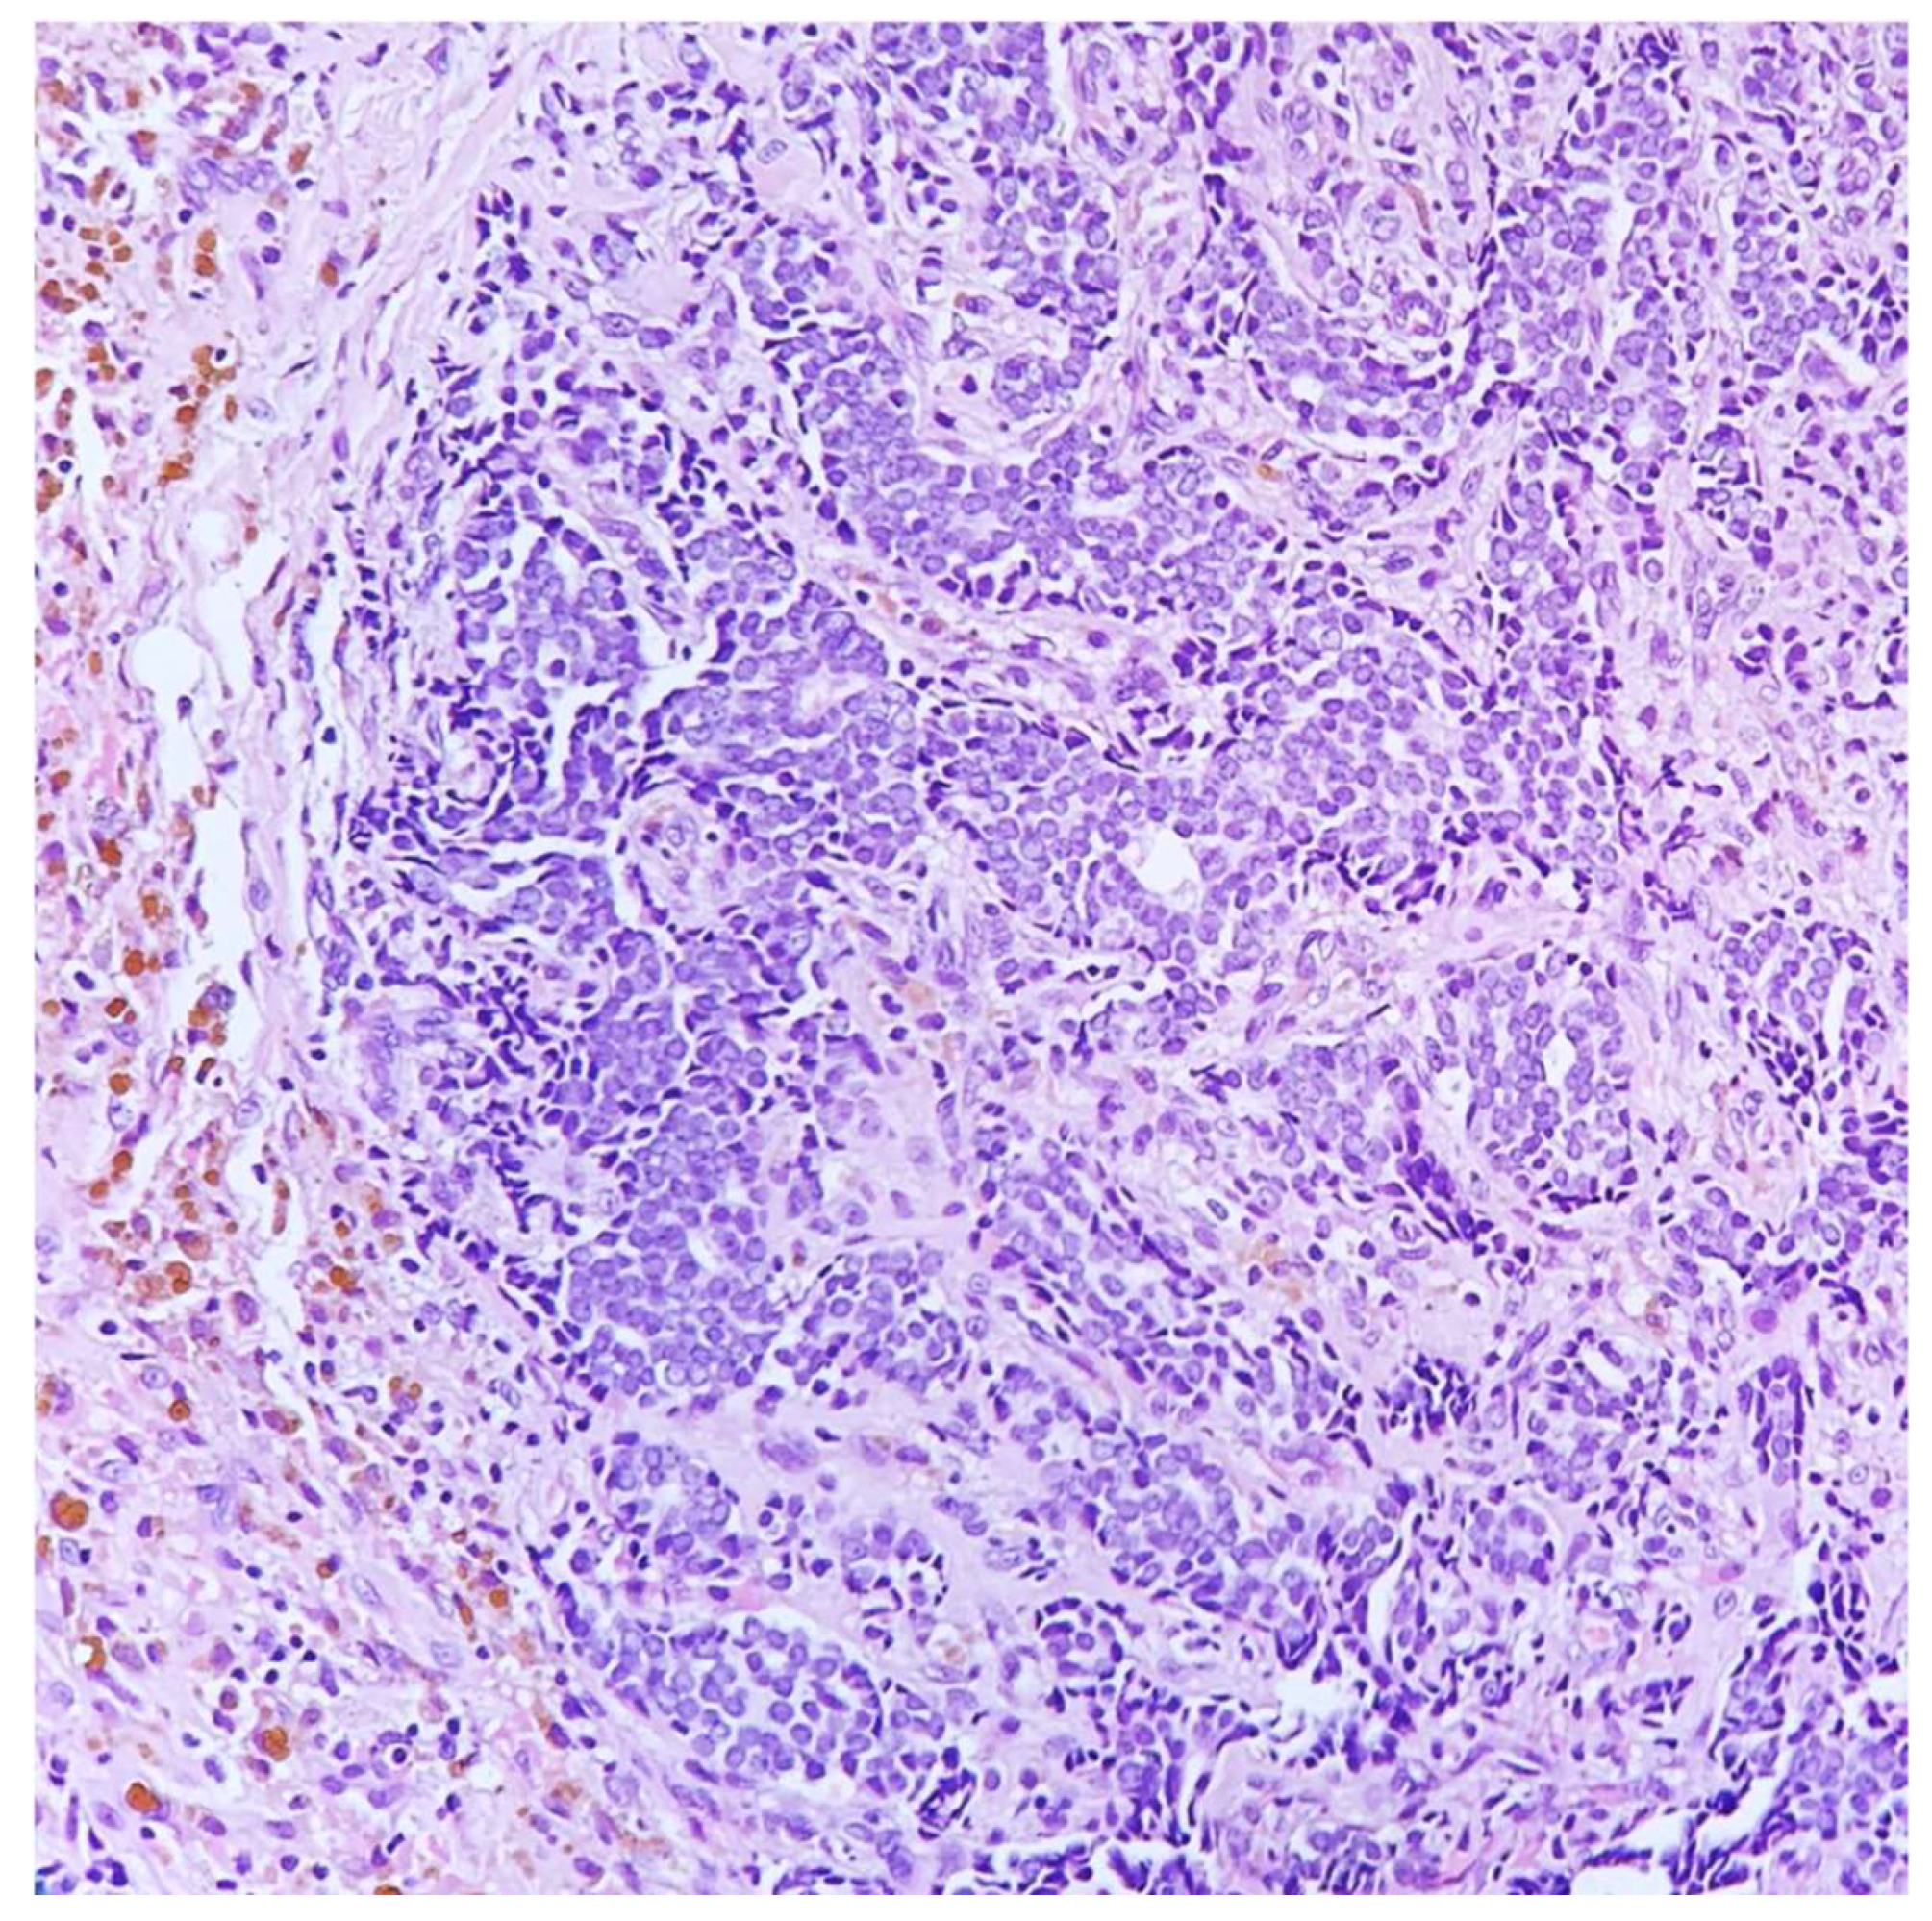

Figure 2. Ultrasound-guided core needle biopsy showing invasive gland-forming carcinoma, associated with erythrocytes, hemosiderin, and many stromal osteoclast-like giant cells (HE, 200×).

A 45-year-old lady, during her screening ultrasonography, was found to have an 8-millimeter solid mass in the upper outer quadrant of right breast, characterized by irregular margins and inhomogeneous internal echoes, suspicious for carcinoma. An ultrasound-guided core needle biopsy of the lesion was performed and a diagnosis of gland-forming breast carcinoma with many erythrocytes, hemosiderin, and stromal osteoclast-like giant cells was rendered. The neoplastic cells showed a moderate grade of atypia. No further assays were performed (Figure 1 and Figure 2).